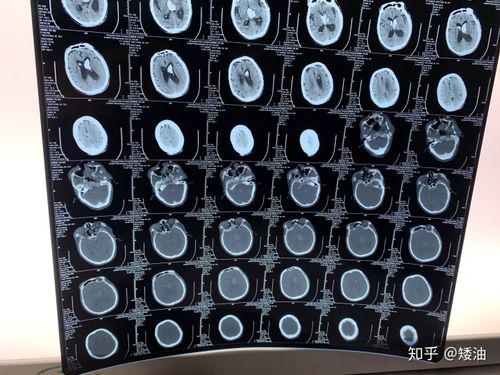

脑部ct照片真实,脑萎缩ct图像

6 个病例学会"脑梗死"的 4大ct 征象

ct提示左侧基底节,丘脑,颞叶,枕叶广泛性脑出血.